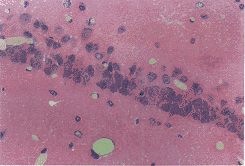

图1 正常对照组海马 CA1区锥体细胞排列整齐而致密 HE×132

图2 假手术7天组海马CA1区锥体细胞数目和形态同正常组 HE×132

图3 VD模型7天组海马CA区锥体细胞排列紊乱,脱失严重,胞核浓染 HE×132

图4 中药防治7天组海马CA1神经元排列较规则,细胞较规则,细胞轻度脱失,部分胞染变深 HE×132